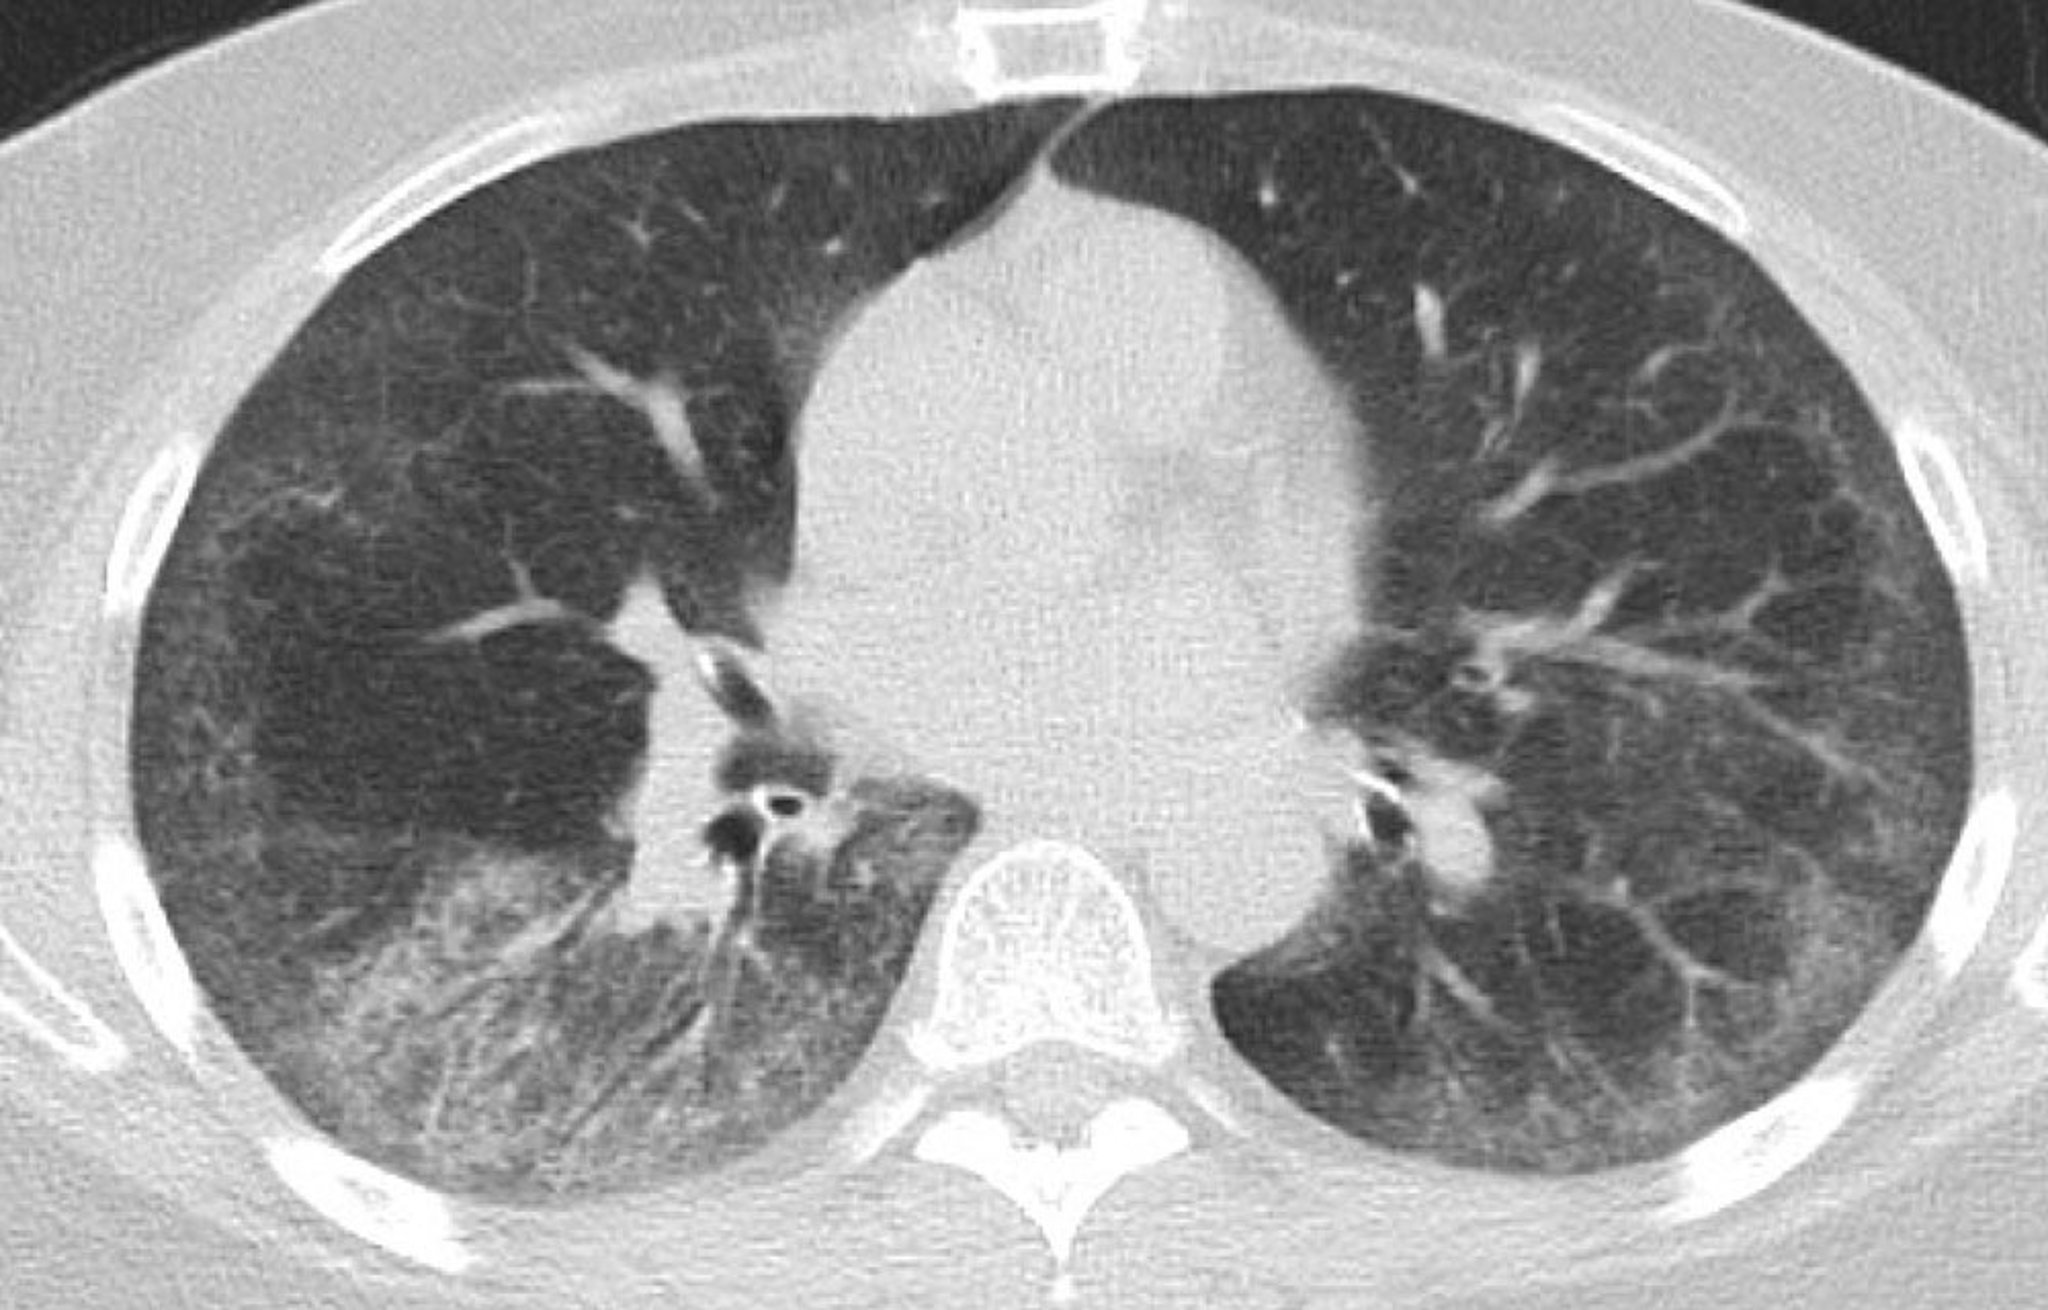

Интерстициальная болезнь легких (КТ органов грудной клетки)

На данном КТ-скане показаны симметричные затемнения обеих нижних долей по типу матового стекла с участками тонкой субплевральной ретикуляции; умеренная тракционная бронхоэктазия в обоих легких с субплевральным сохранением; и несколько рассеянных грудных лимфатических узлов.

Photo courtesy of Kinanah Yaseen, MD.